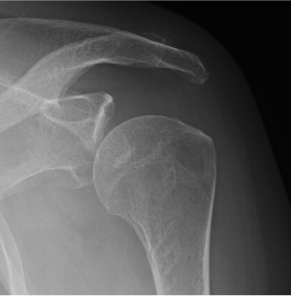

Type IA: Anterior glenoid rim fracture

Xray / CT